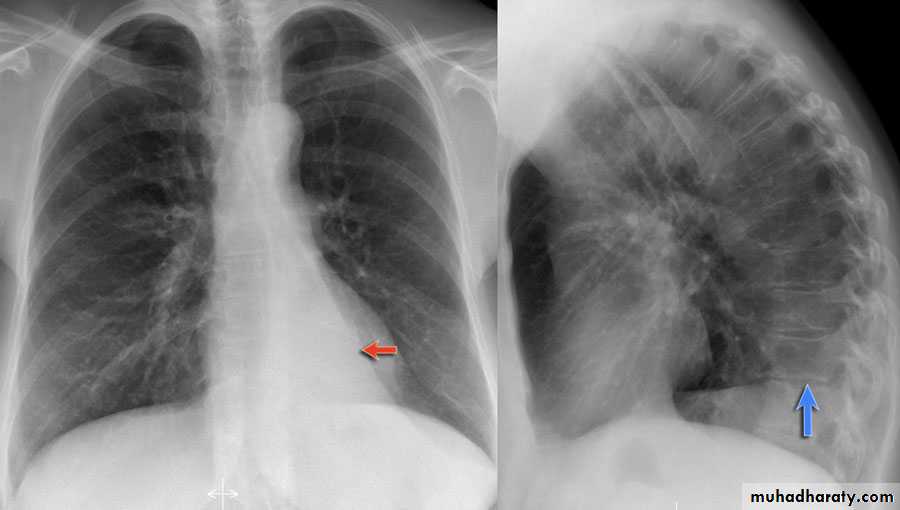

History; too shy to take of his shirt in the pool!